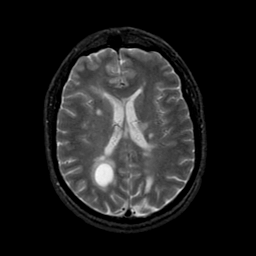

MR Study #21, November 3, 1991 -- Slice #30